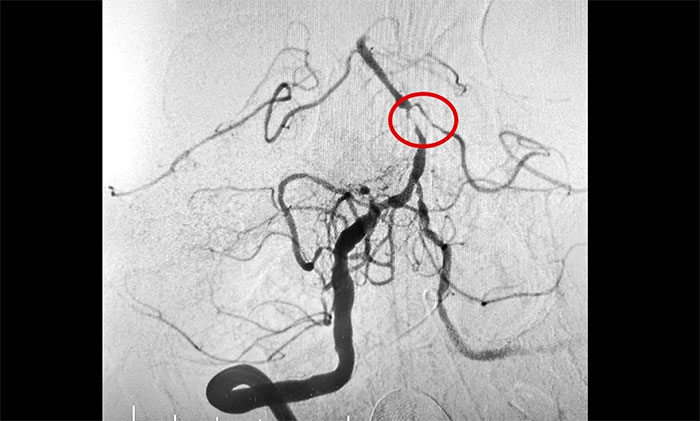

磁共振檢查提示,腦干梗塞軟化灶形成;雙側(cè)大腦半球白質(zhì)多發(fā)腔梗;腦動脈硬化,左側(cè)大腦后動脈纖細遠端未見顯影,右側(cè)大腦后動脈P1段狹窄,左側(cè)椎動脈纖細。DSA提示左側(cè)基底動脈中段次全閉塞,右椎動脈V4段輕度狹窄,左椎動脈V4末段重度狹窄,左小腦前下動脈起始段重度狹窄,右小腦后下動脈起始段重度狹窄,雙側(cè)大腦后動脈多發(fā)狹窄。

席剛明教授充分評估患者的病情及血管情況,本例患者為基底動脈主干病變,呈現(xiàn)為“一線天”樣狹窄,考慮基底動脈重度狹窄為患者再次腦缺血發(fā)作的根源,狹窄處隨時可能形成血栓引發(fā)血管急性閉塞。一旦閉塞,患者將可能出現(xiàn)深昏迷、四肢癱瘓,甚至危及生命,可以說是“命懸一線”,即使僥幸保住性命,大概率也會成為植物狀態(tài)或遺留其他嚴重殘障。

▲ 左側(cè)基底動脈中段次全閉塞